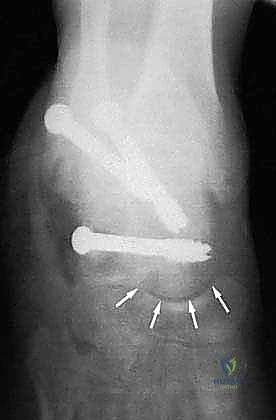

- دمج المفصل تحت الكاحل (Subtalar Arthrodesis):

في الغالبية العظمى من حالات سوء الالتئام، يكون المفصل تحت الكاحل قد تدمر تماماً بسبب الخشونة والاحتكاك. الحل الجذري والنهائي للألم هنا هو "دمج" أو "تثبيت" هذا المفصل. يقوم الدكتور هطيف بتنظيف الغضاريف التالفة بالكامل، ووضع العظام في وضعها التشريحي الصحيح، ثم تثبيتها باستخدام براغي معدنية قوية جداً (Screws) لتلتحم وتصبح عظمة واحدة صلبة خالية من الألم.